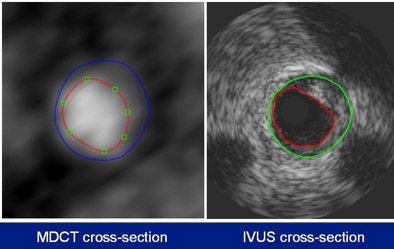

Both IVUS (44-mHz catheter) and 64-detector-row MDCT were performed in 32 symptomatic patients. The MDCT and IVUS datasets of 44 coronary arteries were coregistered using a newly developed and validated fusion technique that derived quantitative parameters from both imaging modalities using a stepwise approach.

"For analysis of the results, several parameters were compared by section, including lumen area, vessel area, plaque area (vessel area minus lumen area), and maximum wall thickness, defined as the distance between the lumen and the vessel wall," Papadopoulou said. "We considered plaque to be present when the maximum wall thickness was above 0.5 mm." This is criterion commonly used for IVUS but it has not been previously used for CT.

Compared with IVUS, 64-detector-row MDCT enabled correct detection in 957 of 1,109 cross-sections containing plaque (sensitivity 86%). In 180 of 255 cross-sections, atherosclerosis was correctly excluded (specificity 71%). At the segmental level, MDCT detected 213 of 220 segments with atherosclerotic plaque (sensitivity 96%), while correctly ruling out the presence of any plaque in 28 of 32 segments, for a specificity of 88%.